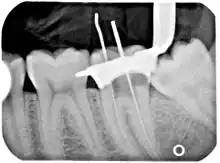

Poor-quality root filling

Another common complication of root canal therapy is when the entire length of the root canal is not completely cleaned out and filled (obturated) with root canal filling material (usually gutta percha). On the other hand, the root canal filling material may be extruded from the apex leading to other complications. The X-ray in the right margin shows two adjacent teeth that had received bad root canal therapy. The root canal filling material (3, 4, and 10) does not extend to the end of the tooth roots (5, 6 and 11). The dark circles at the bottom of the tooth roots (7 and 8) indicated infection in the surrounding bone. Recommended treatment is either to redo the root canal therapy or extract the tooth and place dental implants. Poor quality filling material or sealant may also cause root canal treatment to fail.[47]